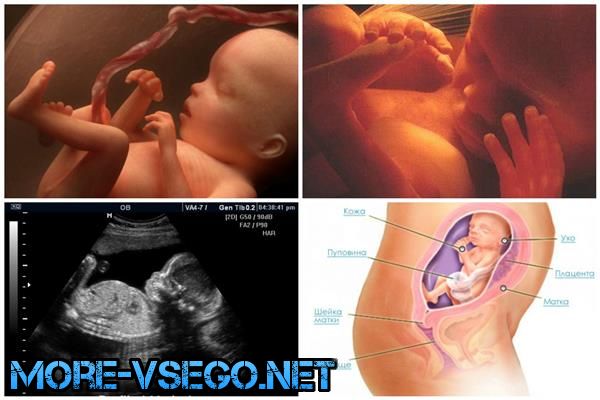

Когда в животе женщины зарождается новая жизнь, этот процесс можно сравнить разве что с волшебством. Организм будущей матери перестраивается на другой лад, поэтому беременность по неделям имеет смысл рассмотреть во всех подробностях. Развитие плода происходит постепенно, одновременно с этим меняются и ощущения женщины.

Беременность по неделям включает в себя развитие эмбриона (плода). Мы опишем его внешний вид, укажем и ощущения женщины. На данном этапе берёт начало формирование скелета младенца, органов ЖКТ, щитовидки, печени, головного мозга.

Беременность по неделям, развитие плода с фото покажется впечатляющим. Плод уже достиг своих первых внушительных размеров, порядка 1,6—2,1 см. По внешнему виду маленькая головка и вытянутое тельце напоминают головастика.